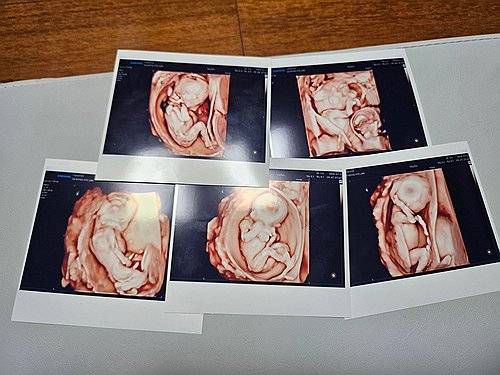

세계적으로도 드문 자연임신으로 생긴 ‘오둥이(새힘·새찬·새강·새별·새봄)’는 지난해 9월 20일 세상의 빛을 처음 봤다. 출산까지의 과정은 순탄치 않았다. 임신 기간 내내 엄마 사공혜란씨는 편한 날이 없었다고 한다. 작은 체구의 엄마 사공씨는 임신 5개월차부터 앉기도 눕기도 힘든 나날을 보내다 임신성 고혈압까지 겹쳐 26주에 제왕절개 수술을 결정했다.